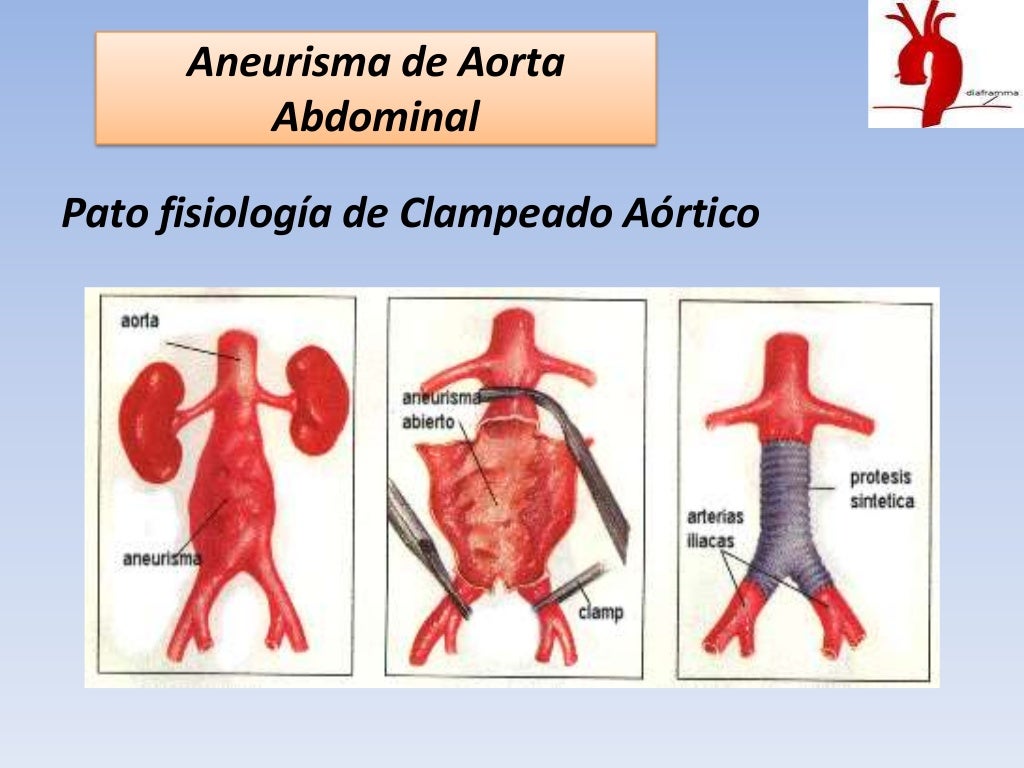

aneurisma de la aorta abdominal La aorta va desde el corazón hasta el. Recibe sangre con gran contenido en oxígeno. Cirugía vascularrupturas de aneurisma de la aorta abdominal: La cirugía de reparación abierta de aneurisma aórtico abdominal (aaa) se realiza para arreglar una parte dilatada de la aorta. Si tienes un aneurisma de la aorta abdominal en expansión, podrías notar lo siguiente: La incidencia de aaai en. En este artículo examen físico pruebas de detección y de diagnóstico ¿quiénes deben someterse a un examen de detección de aneurisma de aorta torácica? Los aneurismas aórticos aneurismas aórticos la aorta, que mide alrededor de 2,5 cm de calibre o diámetro, es la arteria más grande del cuerpo.

Así se interviene el aneurisma de aorta abdominal roto La Verdad

Source: www.laverdad.es